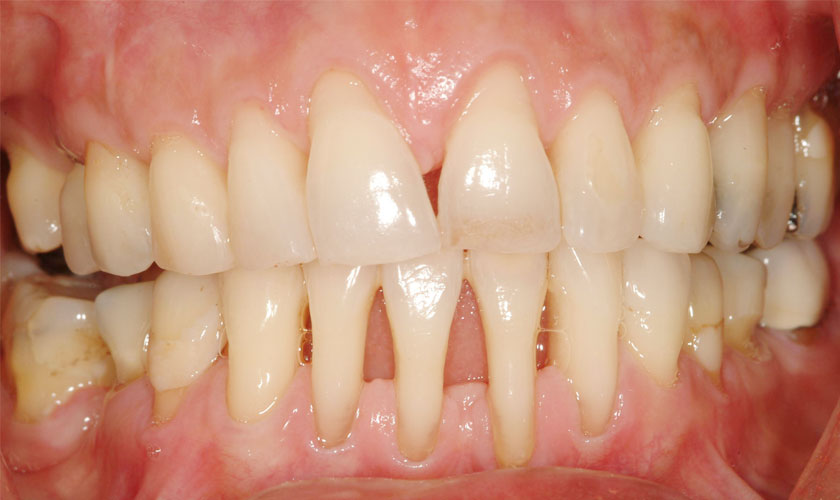

Còn khi bệnh viêm nướu tiến triển thành viêm nha chu thì lúc này mô liên kết giữa nướu và răng bị phá hủy, xuất hiện túi mủ trên nướu, vi khuẩn có hại tiếp tục tấn công khiến nướu dễ bị hoại tử, nguy cơ cao dẫn đến mất răng.

Bệnh viêm nha chu.